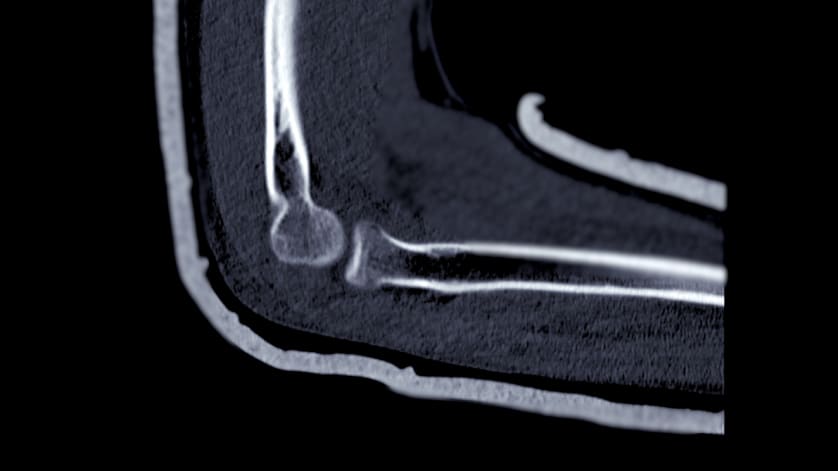

October 02, 2025 Distal vs Shaft Tibia Fractures in Children Open distal tibia fractures in pediatric patients are more severe than shaft fractures. Conexiant